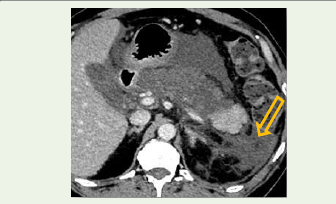

Representative Case Illustration:

A 48-year-old male with a history of chronic alcohol use presented

with acute onset severe epigastric pain radiating to the back, associated

with vomiting. Laboratory evaluation revealed significantly elevated

serum amylase and lipase levels.Contrast-enhanced CT performed on day 5 of symptom onset demonstrated extensive areas of non-enhancing pancreatic parenchyma involving more than 60% of the gland, along with largevolume extrapancreatic necrosis extending into the anterior pararenal space and mesenteric root [Figure 3].

Figure 3: Contrast-enhanced CT image showing extensive extrapancreatic

necrosis with inflammatory fat stranding and necrotic collection (arrow) in the

retroperitoneal spaces, representing a severe case described in the Results

section [8,12].